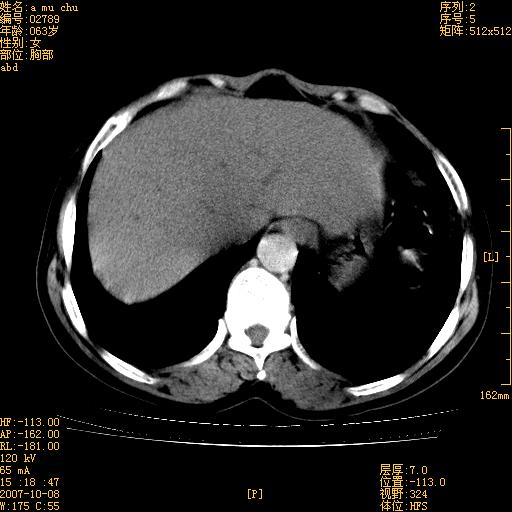

以下是引用王维浦在2007-10-17 21:02:00的发言:[br]胆囊增大,囊壁明显不规则增厚,邻近肝组织浸润,肝内外胆管无扩张。诊断:胆囊ca;[br]胰头软组织肿块影,考虑是由转移肿大的胰后淋巴结、没有肠道准备的十二指肠及胰头共同形成。[br]

以下是引用zhangzexing在2007-10-18 7:13:00的发言:[br]支持胰头占位,慢性胆囊炎. 2.肝左叶前外侧段占位,血管瘤?建议增强

以下是引用影像实习生在2007-10-17 19:49:00的发言:[br]支持胰头占位,慢性胆囊炎. 2.肝左叶前外侧段占位,血管瘤?建议增强.

以下是引用刘振江在2007-10-17 19:42:00的发言:[br]没有增强,胰头癌?胆囊及肝左叶占位?